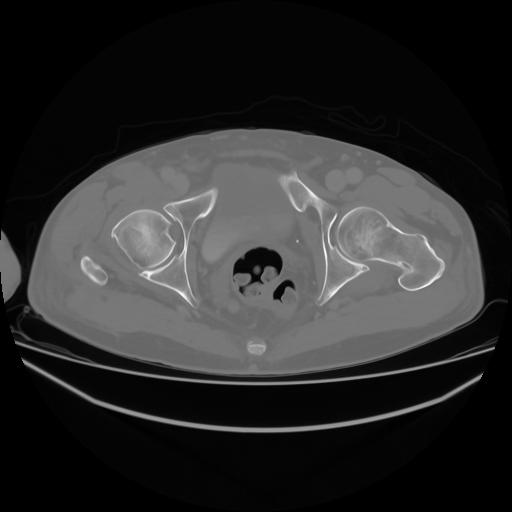

4 CUERPO,CE,Axial,3.0,CUERPO,,